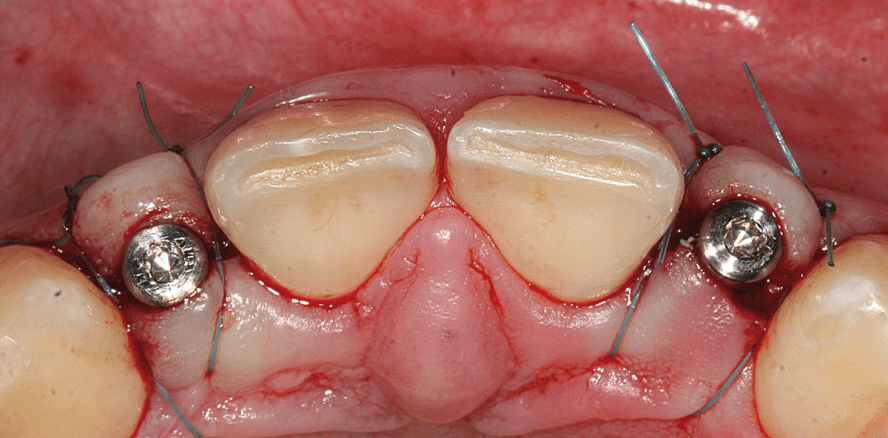

Zur besseren intraoperativen Orientierung bei gleichzeitiger Vermeidung von ästhetisch beeinträchtigenden Narben erfolgt beidseits eine minimale krestale Schnittführung ohne Entlastungsinzision (Abb. 5a und b). Die Aufbereitung der Implantatlager erfolgt mit dem 2-mm-Spiralbohrer in ganzer Länge und nur im oberen Drittel mit dem system typischen zweiten Stufenbohrer mit Durchmesser von 2,4/2,8 mm (Abb. 6 und 7). Dank des spezifischen Implantatdesigns des NobelActive Implantates mit seinem konischen Kern und den weit ausladenden Gewindeflanken resultiert eine hohe primäre Stabilität von jeweils > 45 Ncm, die für die angestrebte Sofortversorgung sicher ausreichend ist (Abb. 8). Die Insertion der Implantate erfolgt zunächst maschinell mit dem grünen Winkelstück, die exakte minimal subkrestale Implantatpositionierung dann mit der bis 70 Ncm drehmomentkalibrierten Handratsche (Abb. 9 und 10). Der gut adaptierende Wundverschluss beendet den chirurgischen Eingriff, bevor die „Open Tray“-Abdruckpfosten mit ihren Retentionselementen eingesetzt werden und mit einem konfektionierten, individuell perforierten Kunststofflöffel nach der Pick-up-Technik die Abformung für die provisorische Sofortversorgung durchgeführt wird (Abb. 11 und 12).Provisorische Sofortversorgung Binnen 24 Stunden werden im Labor direkt auf Implantatniveau verschraubte provisorische Kronen angefertigt. Dank der günstigen Konfiguration des Alveolarfortsatzes und der präzisen Ausrichtung der Implantate kommen die Schraubenzugänge palatinal hinter der Schneidekante zu liegen (Abb. 13 und 14). Aus der direkten Verschraubung resultieren Vorteile in mehrfacher Hinsicht: Die Konstruktion ist unkomplizierter, da die Krone nur aus einer Komponente besteht und Fehlpassungen aufgrund des konfektionierten Anschlusses an das Implantat ausgeschlossen sind. Es besteht nicht die Gefahr, Zement unter das unmittelbar postoperativ nur ganz locker anliegende Weichgewebe zu überpressen, und die kontrollierte Abnahme der Krone ist jederzeit ohne Beschädigung oder forcierten Aufwand möglich, ohne eine ungewollte Lockerung zu riskieren. Der Verschluss der Zugangskavität erfolgt mittels eines kleinen Wattepellets und einer Kompositfüllung (Abb. 15–17). Die radiologische Kontrolle zeigt die genaue epikrestale Positionierung der Implantate und den exakten Sitz der provisorischen Kronen auf den Implantaten (Abb. 18 und 19). Nach dreiwöchiger weiterer Abheilung ist es bereits zu einem signifikanten  Rückgang der postoperativ bei Eingliederung noch deutlich geschwollenen Gingiva gekommen (Abb. 20).